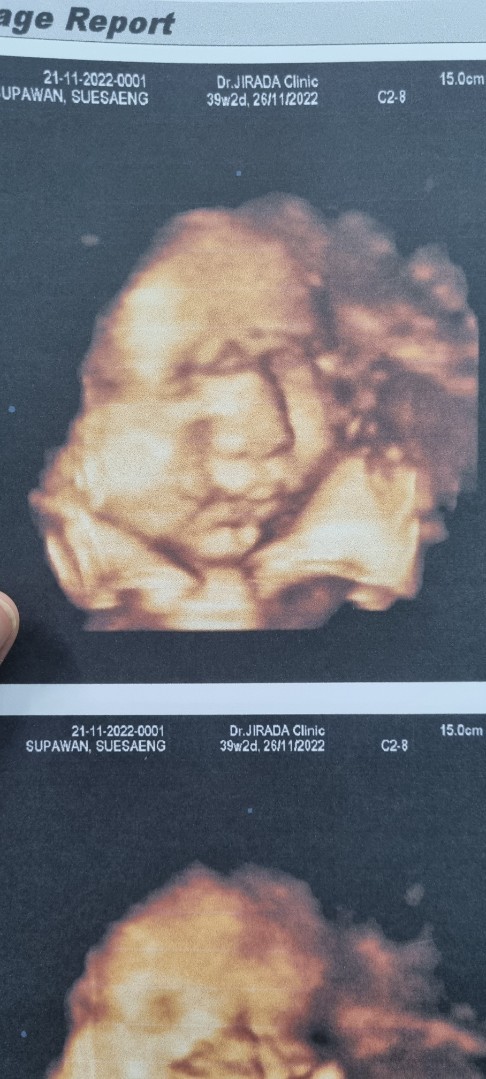

39+2 ค่า